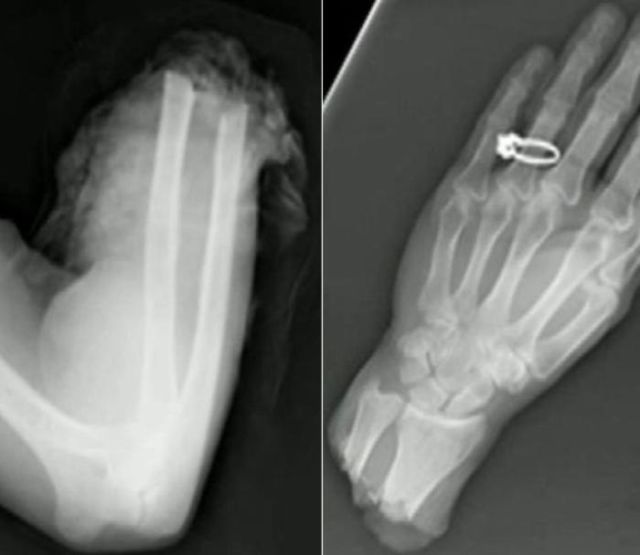

These x-rays will make you wonder how this could ever have happened in the first place.